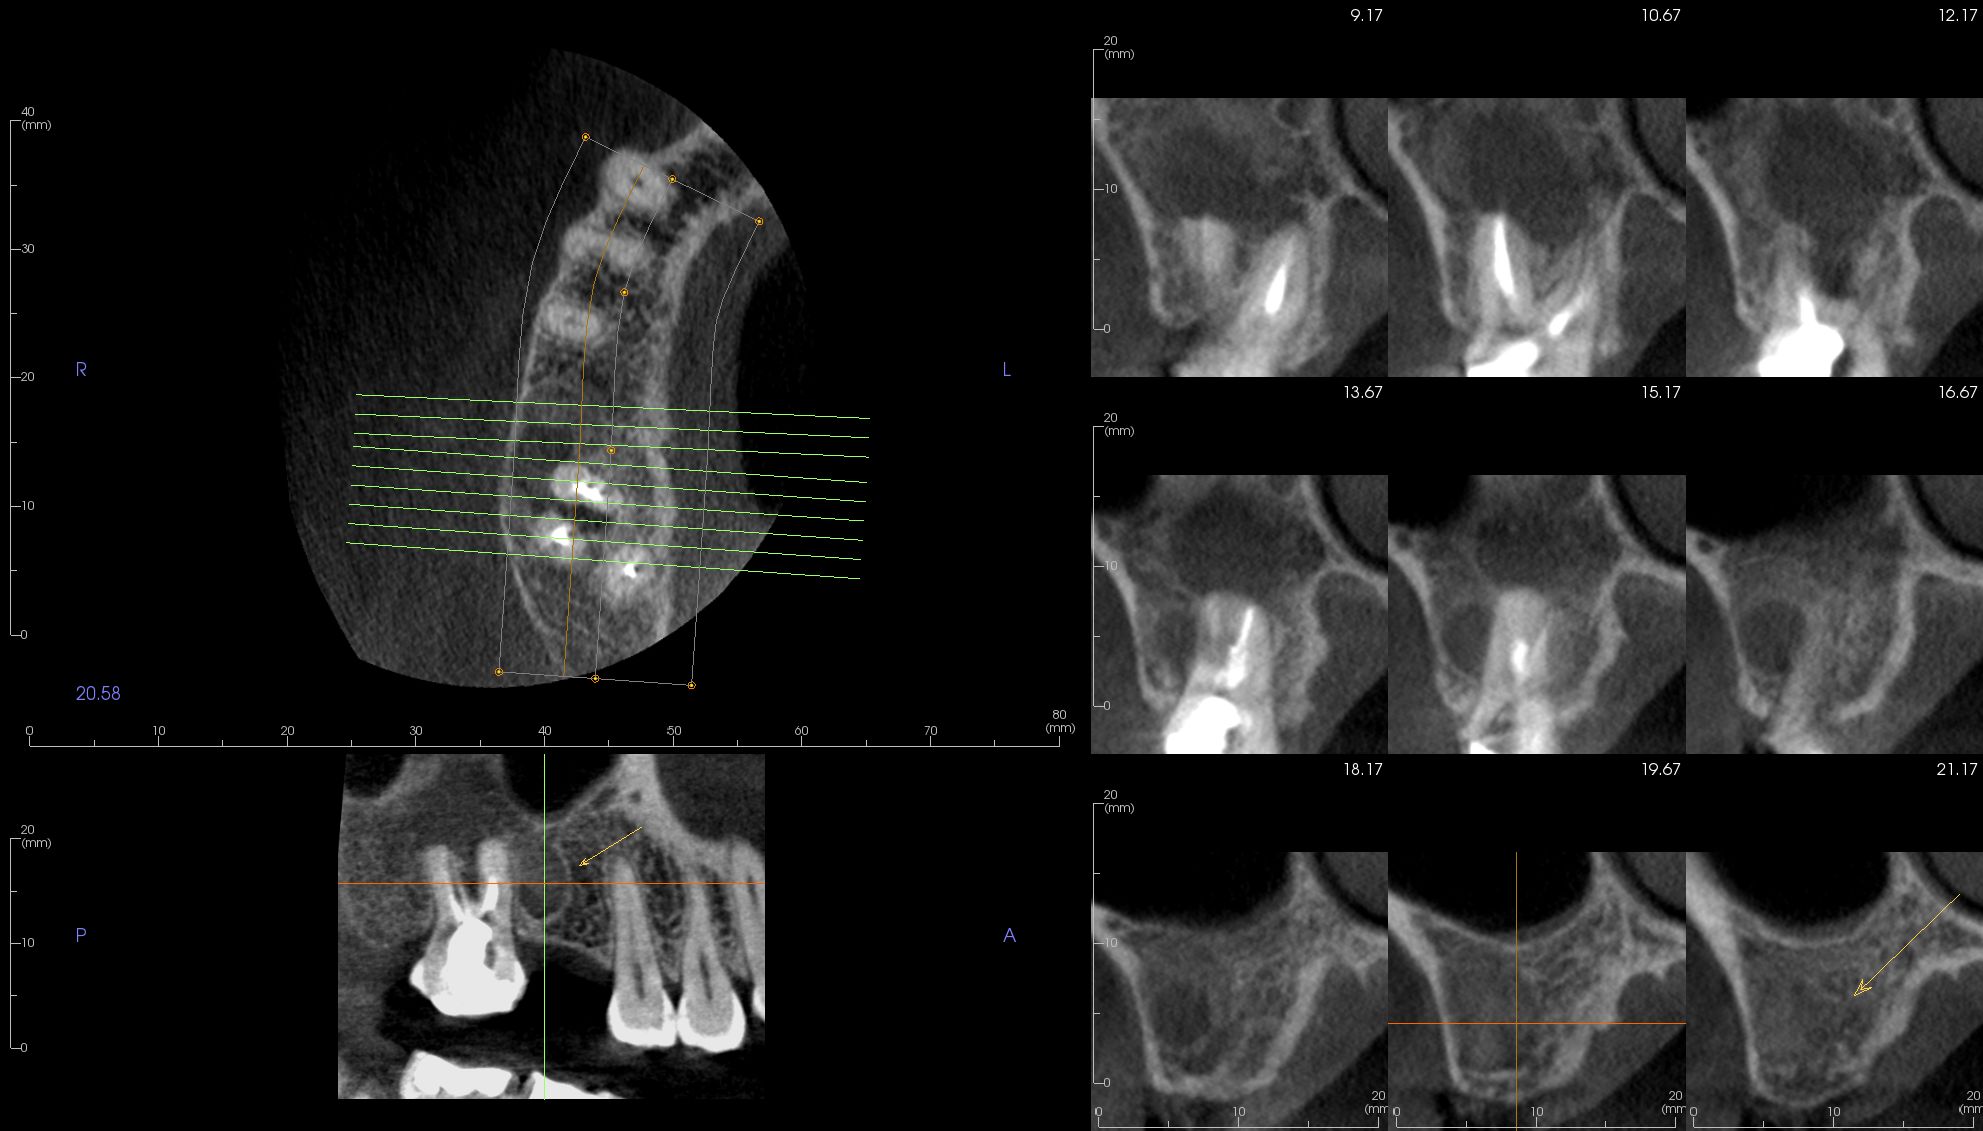

Image Portfolios visually communicate the imaging goals to you and your patient.